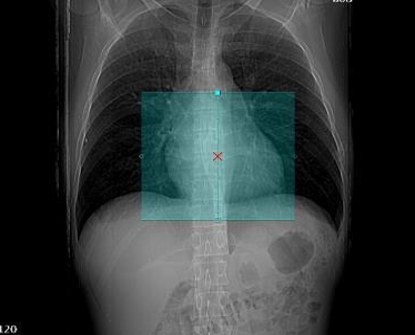

Iso-center the heart: Standard practice is to center the heart in the imaging volume. Some vendors recommend a slight right shift to center the heart more precisely.

Image source: GE HealthCare GmbH